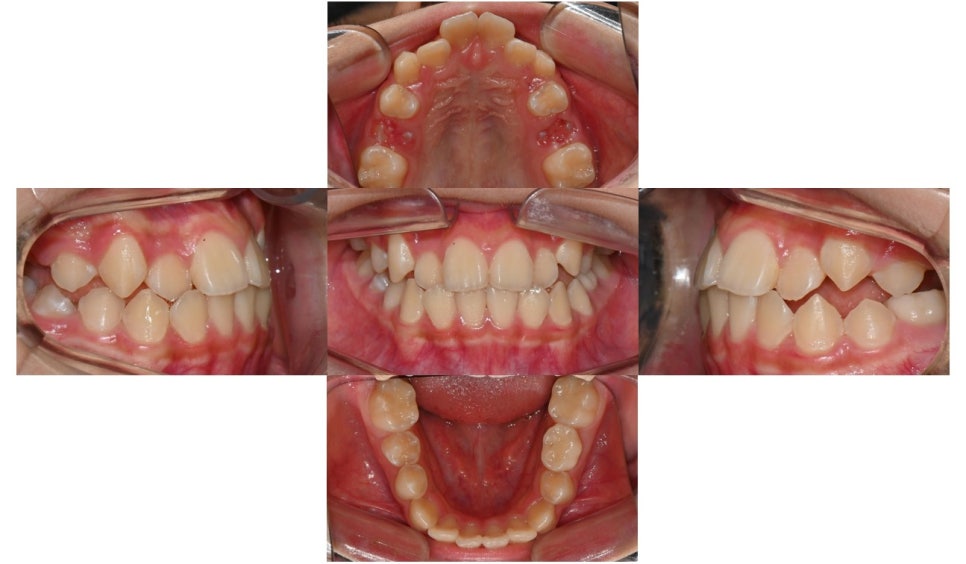

2025년 2월 초진

본 환자는 만 10세 남환으로 소아치과에서 부정교합으로 진단받고 치료를 위해 내원하셨습니다. 정밀검사 결과 제3급 부정교합을으로 송곳니와 어금니는 3급 교합관계를 보이고 있었습니다. 앞니의 반대교합이 심하고 아래턱이 현저하게 많이 발달했을 경우에는 위턱뼈의 확장과 성장교정을 먼저 시행하는 것이 필요합니다.

그러나 본 환자와 같이 제3급 부정교합 양상이 심하지 않은 경우에는 인비절라인 퍼스트 장치로는 악궁의 확장과 치아 배열을 얻고, 페이스 마스크로 위턱뼈의 성장을 촉진시키는 결과를 기대할 수 있습니다.

위 사진과 같이 송곳니 부위에 페이스 마스크를 착용하기 위한 고무줄을 걸 수 있는 고리를 부여하였습니다. 하루 8~10시간 정도 밤에 잘 때 착용하도록 함으로써 성장이 진행될 때 일종의 유지장치 개념으로 위턱뼈의 성장을 자극할 수 있도록 하였습니다.